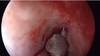

Na imagem está sendo realizado um Draf III. Qual estrutura foi identificada?

Primeira fibra do nervo olfatório (limite posterior da dissecção).